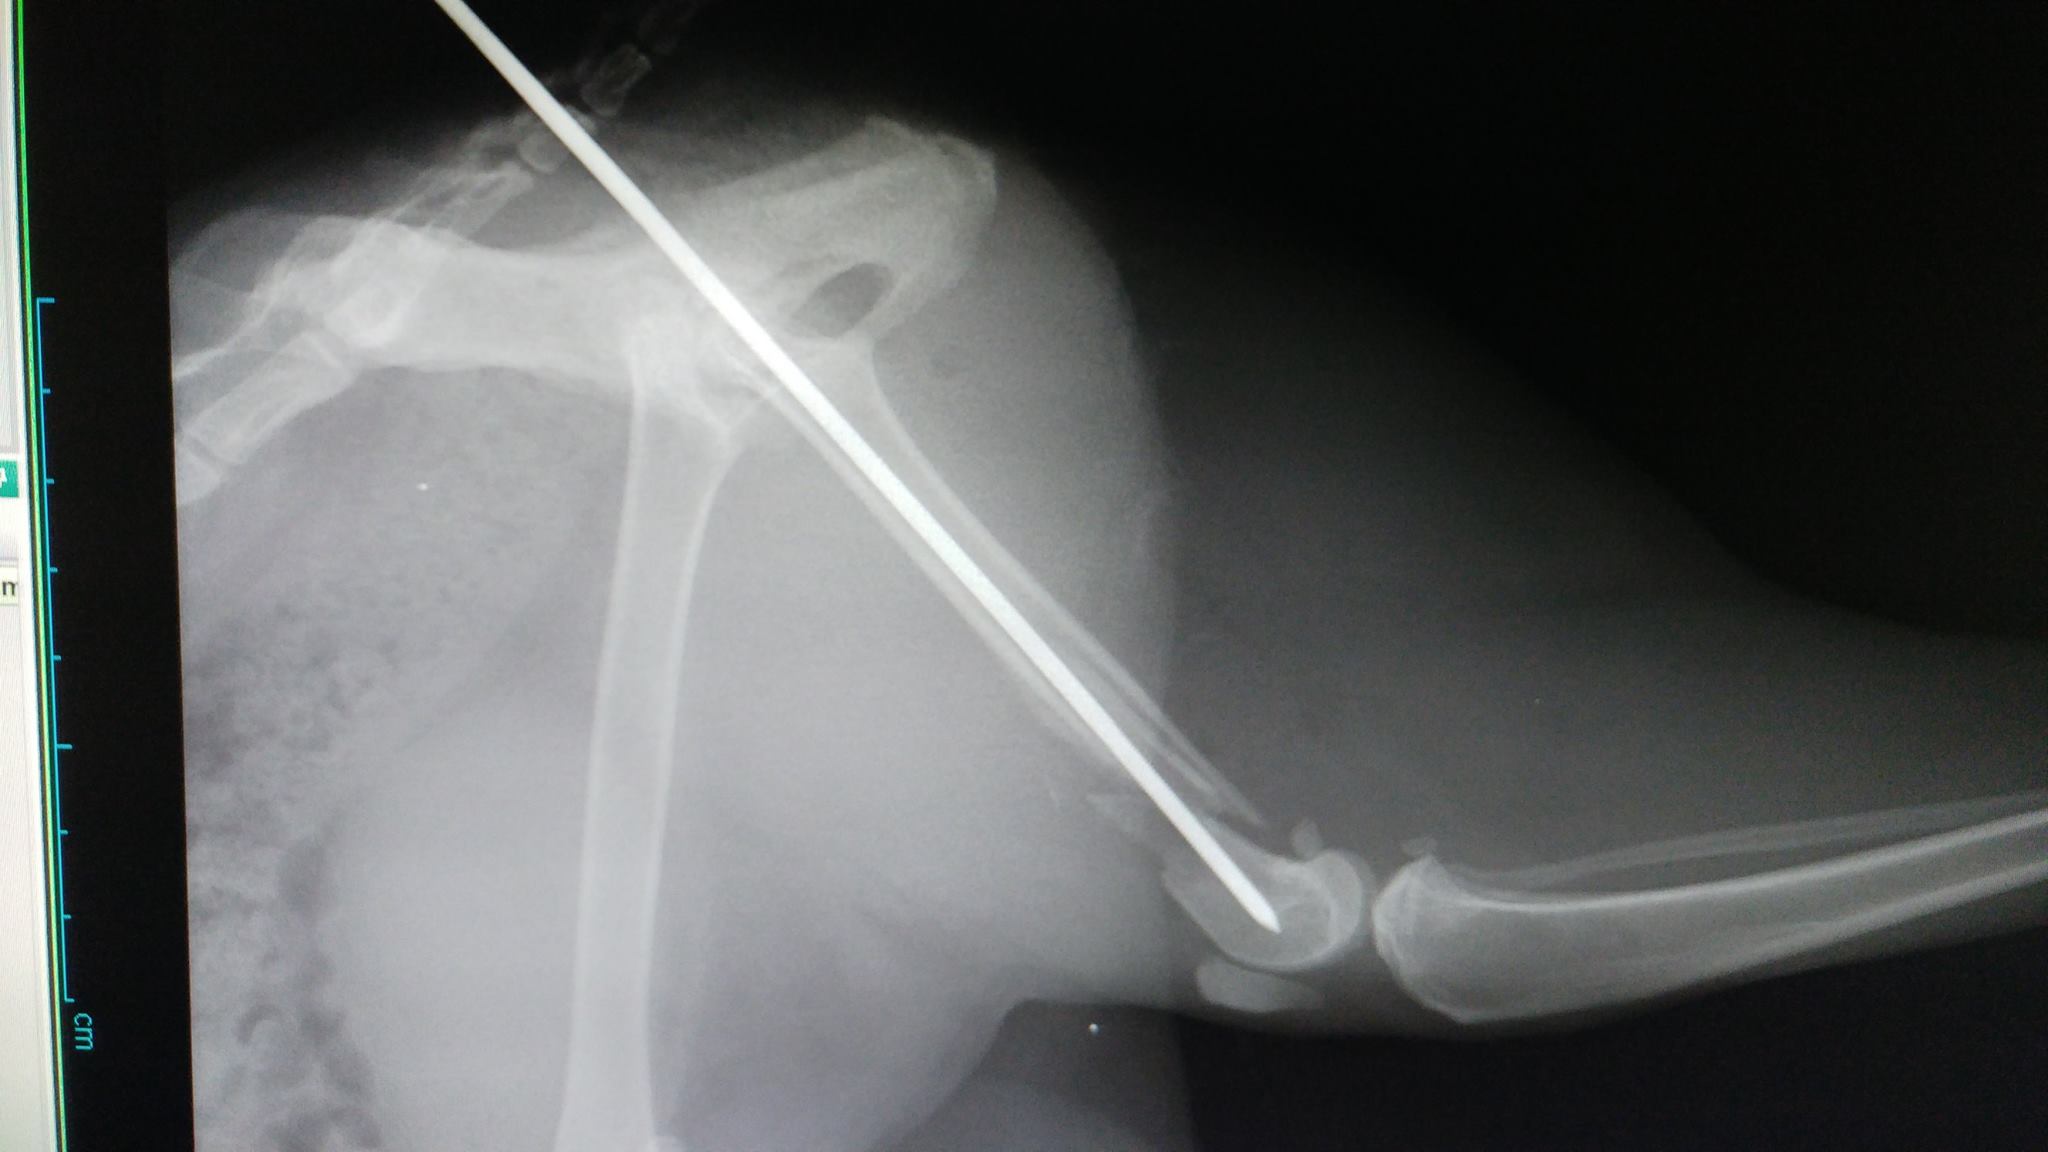

'זילולה' נעלמה ליותר משבוע וחזרה כשהיא לא דורכת על רגלה האחורית. בבדיקה וצילום במרפאה התגלה ש'זילולה' כנראה נדרסה ושברה שבר נוראי את רגלה. היא כנראה שברה את רגלה ביום שנעלמה, מאחר והשבר כבר לא היה "טרי", מה שסיבך מאוד את הטיפול בה. ואם לא די בכך, התקציב הטיפולי של 'זילולה' היה מוגבל ולא איפשר תיקון אורטופדי מתקדם.

כדי להציל את הרגל שלה, ביצענו ניתוח אורטופדי הרואי ומורכב, בו הצלחנו להחזיר את העצמות למנח כמעט אנטומי. וזאת כנגד כל הסיכויים כי השבר כבר התחיל בתהליך איחוי.